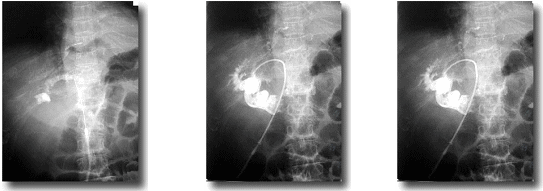

PTCD(経皮経肝胆道ドレナージ)